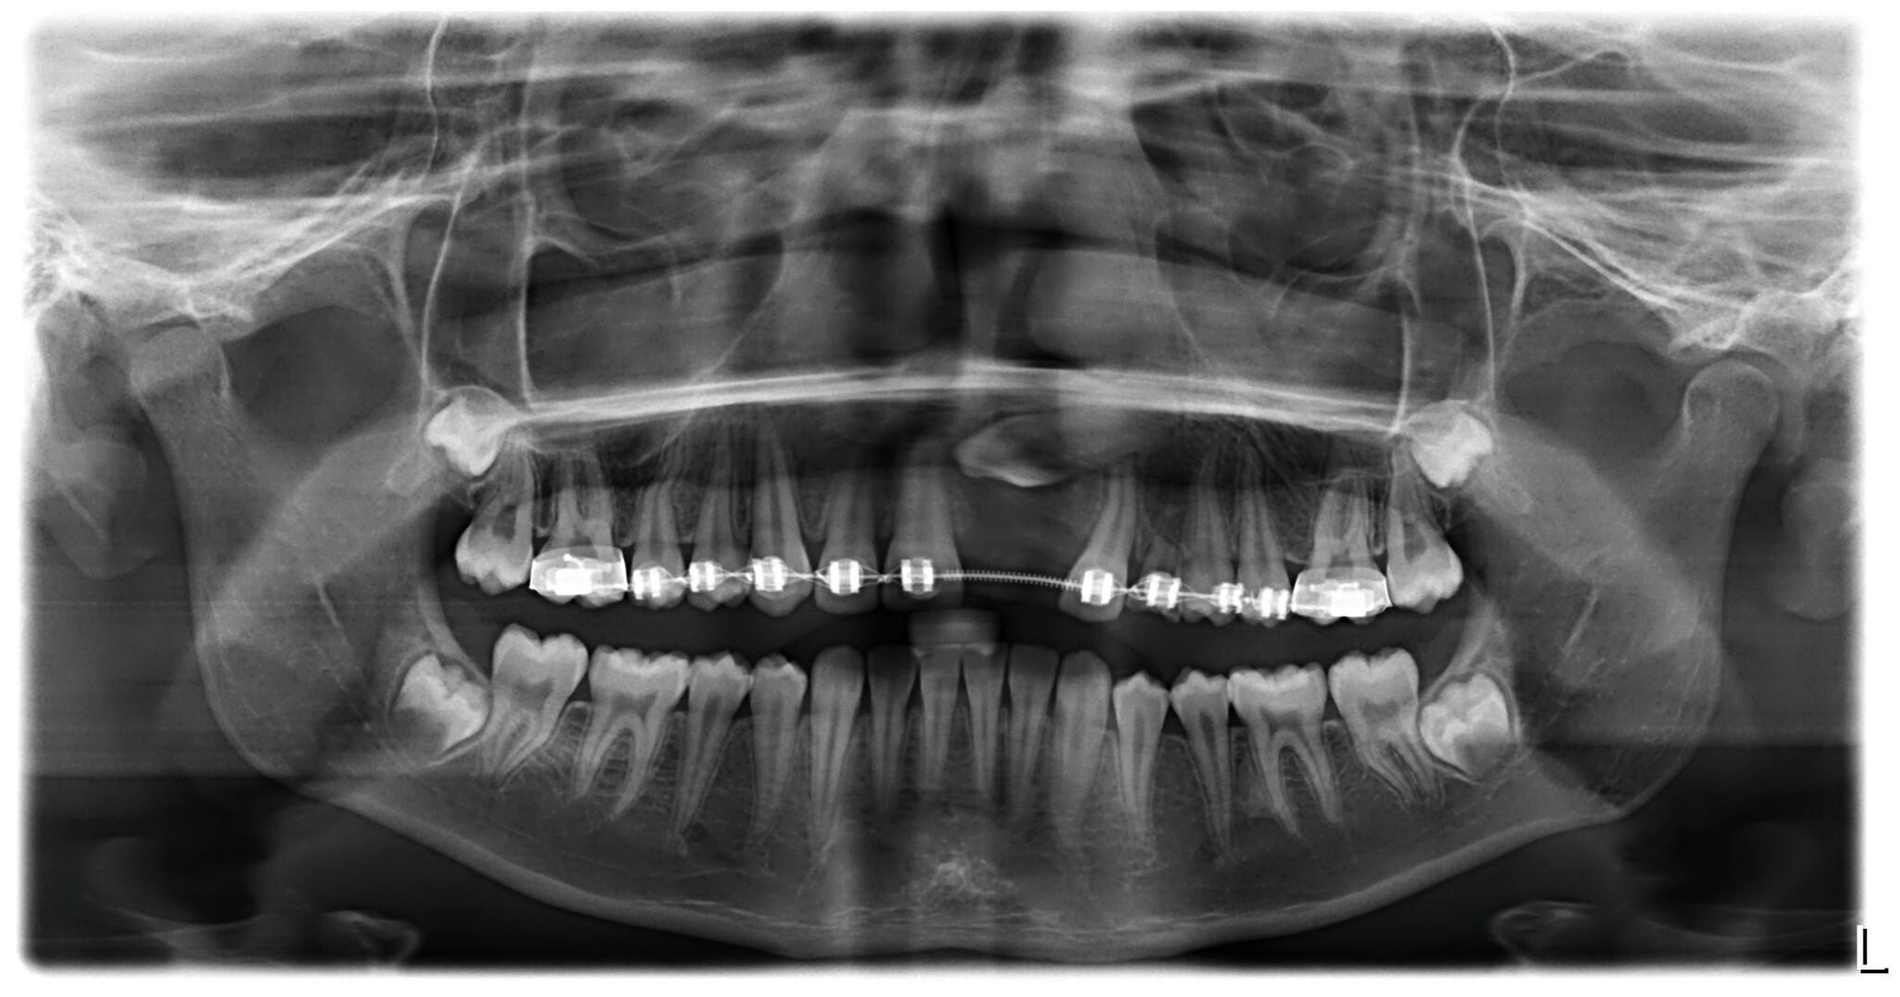

Die kieferorthopädische Behandlung der Patientin wurde im Mai 2018 (alio loco) begonnen. Zu diesem Zeitpunkt war die Patientin zehn Jahre alt. Bei der Erstellung des Behandlungsplans wurde der Fall initial als fehlender linker Eckzahn im Oberkiefer diagnostiziert. Vor der Extraktion des Schneidezahns wurde eine CT-Aufnahme durch den Erstbehandler angewiesen. Die Bildgebung ergab, dass der obere mittlere Schneidezahn sowie der Eckzahn auf der linken Seite betroffen waren (Abbildung 1). Die Patientin wurde daraufhin vom Erstbehandler zur Extraktion des impaktierten Zahnes 21 überwiesen.

Um die Position des impaktierten Eckzahns zu beurteilen, wurde zehn Monate nach der Extraktion des Schneidezahns eine weitere Panoramaröntgenaufnahme angefertigt, Die Position des Eckzahns war unverändert, jedoch hatte die Extraktion des impaktierten oberen Schneidezahns zu einer signifikanten Knochenresorption und Atrophie des Alveolarkamms (Abbildung 3) geführt.

Nach einer detaillierten Analyse des Falles wurde als Ziel der Behandlung die chirurgische Freilegung und Aufrichtung des impaktierten Eckzahns im Bereich des extrahierten linken mittleren Oberkieferschneidezahns festgelegt. Um die Höhe und die Breite des Alveolarkamms wiederherzustellen und eine adäquate Unterstützung der Gingiva zu gewährleisten, war die Augmentation des Alveolarkamms notwendig. Die Patientin wurde dafür an die Klinik für Mund-, Kiefer- und Gesichtschirurgie des Universitätsklinikums des Saarlandes überwiesen.